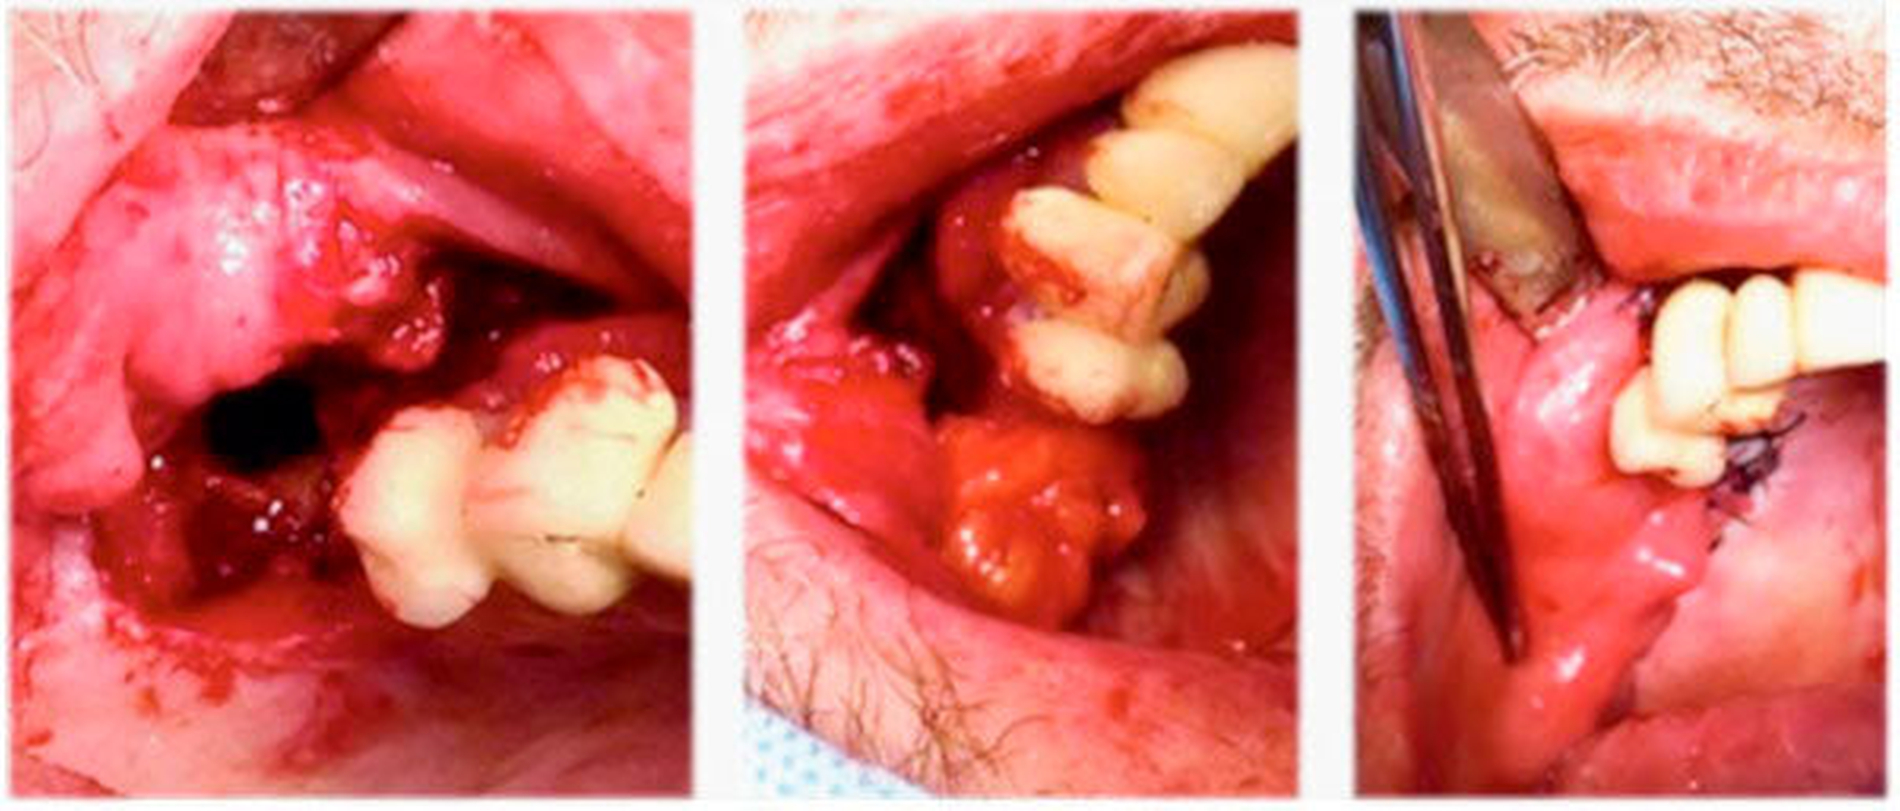

Die bestehende Mund-Antrum-Verbindung wurde nach Rücksprache mit dem Patienten am vierten stationären Tag in Lokalanästhesie geschlossen. Im Einzelnen wurden die Wundränder angefrischt, der Bichat‘sche Fettkörper dargestellt und mit Vicryl eingenäht, bevor der abschließende plastische Verschluss mit horizontalem Verschiebelappen und Periostschlitzung durchgeführt werden konnte.

Nach erfolgter Akutversorgung wurde die Orbita-Kieferhöhlen-Verbindung zunächst belassen. Ähnlich wie bei einer Orbitabodenfraktur heilt das Periost in der Regel über den Defekt und kann diesen im Verlauf luftdicht verschließen [Deichmüller et al., 2018]. Die Mund-Antrum-Verbindung stellt jedoch eine komplexe Wundheilungsstörung in der Mund-Kiefer-Gesichtschirurgie dar. Aufgrund der kontaminierten Kieferhöhle kommt es häufig zu erschwerter Wundheilung und einem verzögertem Verlauf [Dym et al., 2012].

Der Verschluss erfolgte im entzündungsfreien Intervall. In einfachen Fällen kann der Wundverschluss des Knochendefekts mit einem einfachen Mukoperiostlappen durchgeführt werden [Visscher et al., 2010]. Im vorliegenden Fall wurde jedoch aufgrund des bereits alio loco erfolgten, frustranen Deckungsversuchs ein schichtweiser Wundverschluss mit dem Bichat´schen Fettkörper durchgeführt. Diese Methode mit zweischichtigem Verschluss stellt in der Literatur die Methode der Wahl dar und zeigt die besten Ergebnisse [Kim et al., 2017]. Im Verlauf zeigte sich nun ein regelrechter Verlauf und dem Patienten stehen die üblichen Weiterbehandlungsoptionen zur Verfügung.